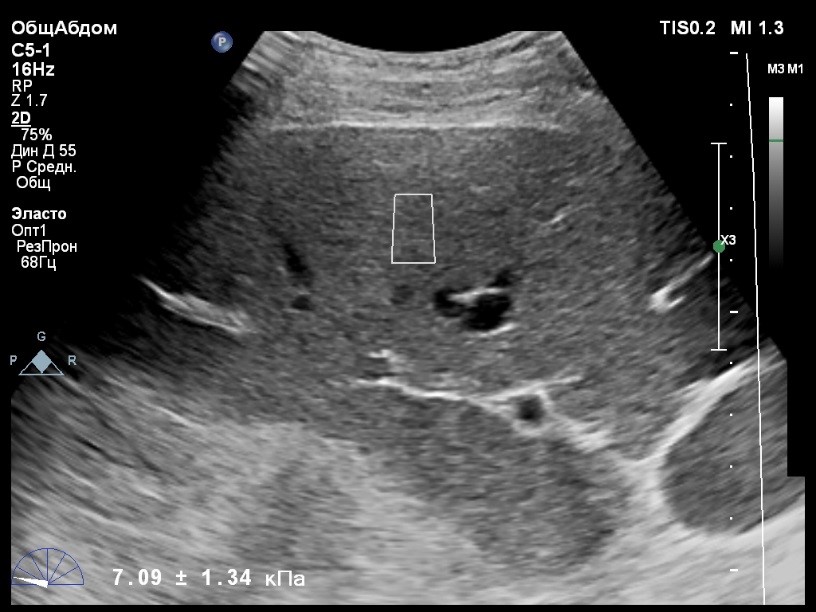

Пациент обратился к доктору с направлением на исследование степени жесткости печени в июне 2017 года. Из истории болезни, пациент страдает Гепатитом С с 2014 года. Лечение не получал. Транзиентная эластография показала не коррективные значения степени жесткости печени по причине сопутствующего поликистоза печени. На момент настоящего исследования, пациент не принимал пищу на протяжении 4 часов, АСТ, АЛТ не превышают патологических значений. Для оценки жесткости была выбрана технология компании Philips ElastPQ (точечная эластография) и прибор компании Philips Epiq 7 Исследование было проведено в соответствии с клиническими рекомендациями для ультразвуковых приборов компании Philips. В результате исследования были получены следующие результаты:

| 1 [7.95] kPa | 2 [8.73] kPa | 3 [8.11] kPa |

| 4 [9.32] kPa | 5 [8.05] kPa | 6 [9.52] kPa |

| 7 [8.66] kPa | 8 [7.36] kPa | 9 [8.54] kPa |

| 10 [8.30] kPa | 11 [6.56] kPa | 12 [7.14] kPa |

| 13 [7.47] kPa | 14 [6.56] kPa | 15 [6.56] kPa |

Стандартное Отклонение [0.85] kPa Медиана Жесткости [8.05] kPa Фактор Качества IQR/Med 10%

Зона интереса расположена на более чем на один сантиметр глубже капсулы, параллельно ходу луча, в середине изображения, в участке печени лишенном кист.

Капсула видна как белая линия перпендикулярная ходу ультразвукового луча, исследования производятся приблизительно в одном и том же сегменте печени.

Стандартное отклонение (2,26 kPA) не превышает 30 процентов от полученного значения (8,54 kPA).

Для интерпретации полученных клинических данных были использованы Рекомендации по проведению эластографии сдвиговой волной для оценки жесткости печени при использовании ультразвуковых аппаратов компании Филипс с примером протокола. Техническая сложность проведения слепой эластометрии печени связана с сопутствующим поликистозом органа и диагностическим методом выбора в данной ситуации является Эластография с возможностью визуального контроля положения контрольного объема. Подготовка пациента соответствовала проводимому исследованию. Представленные слайды проведенного исследования свидетельствуют о правильном техническом исполнении проб, отсутствием в поле контрольного объема кистозных образований, что позволяет заключиться о достоверности полученных измерений. Таким образом, учитывая полученную медиану жесткости на уровне 8,05 кРа (6.56 – 9.52 kPa) и уровень стандартных отклонений не превышающих 30%, полагаю, что уровень степени фиброза соответствует стадии F2. Заведующий отделением УЗД МЦ «Асклепий», Глушенко Д. Е.